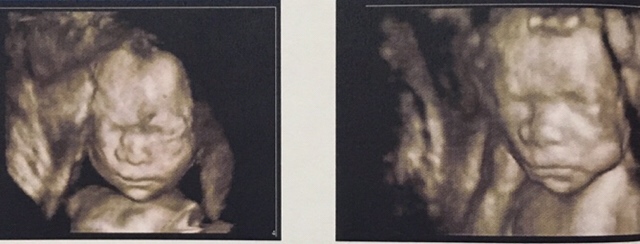

宝宝3天